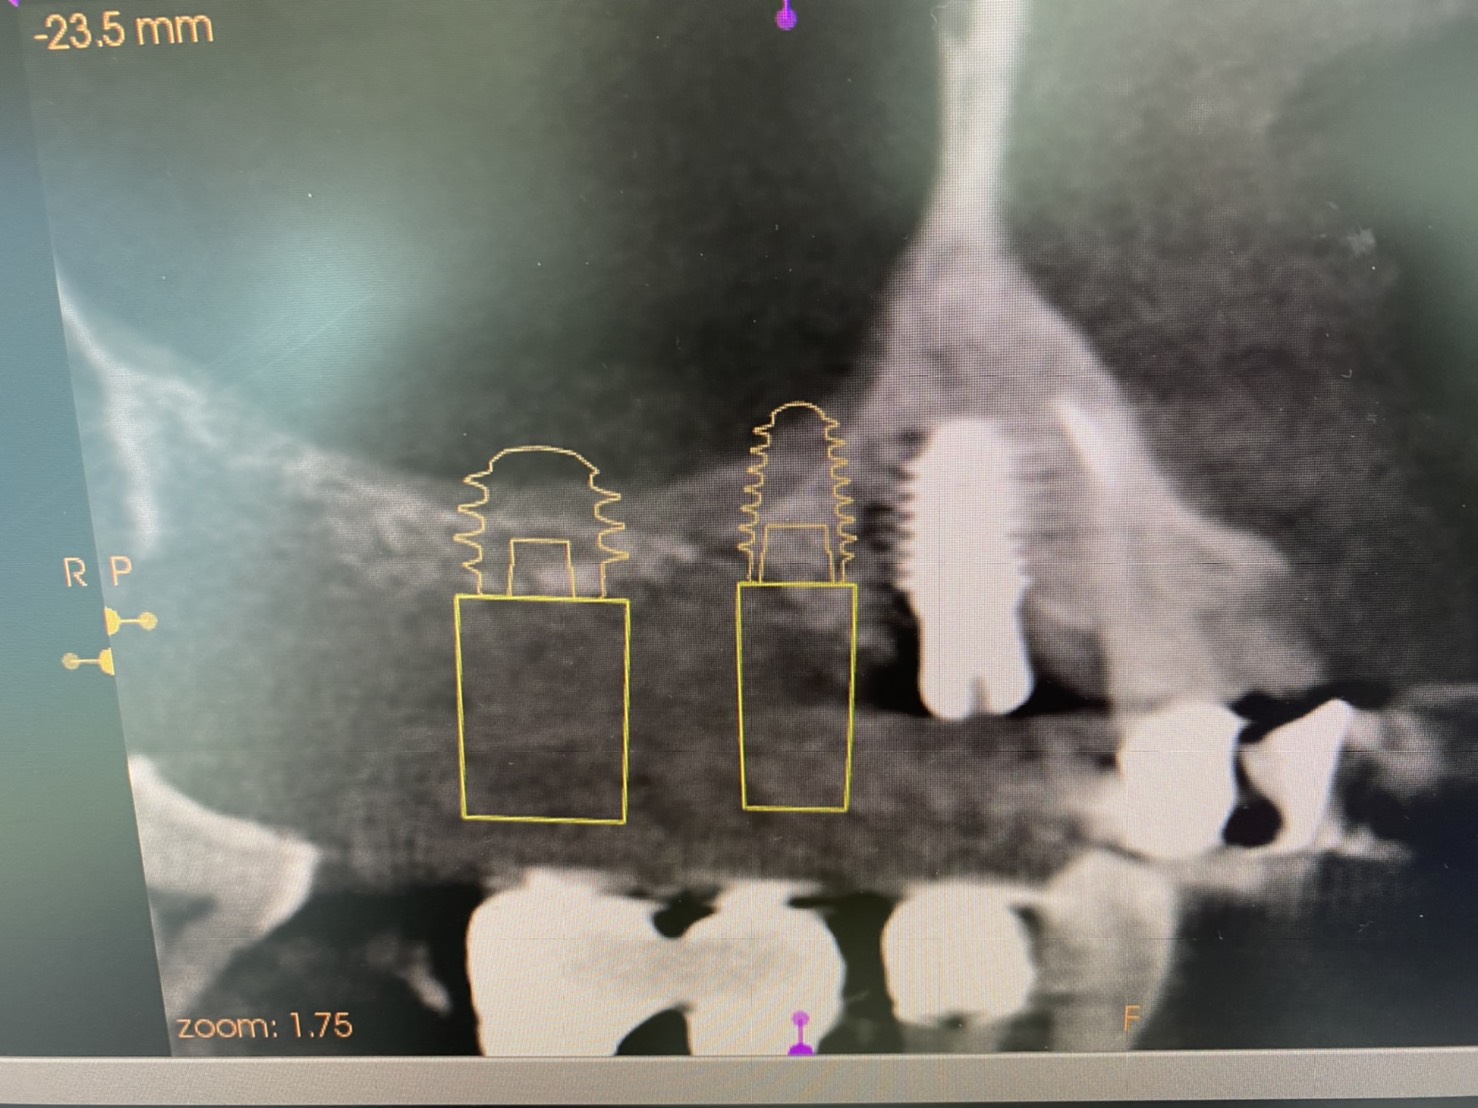

ソケットリフト.インプラント

本日は残存骨が希薄な部位(骨がない)に対するインプラントオペ.

ソケットリフト法を併用した2本同時埋入する非常に難易度の高いオペが須田寛昌執刀医により行われました。

(右上5.6番のインプラントオペ)

術前CT画像に示すよう、残存骨の高さは僅かしかないので、造骨の為にソケットリフトを併用しなければなりません。